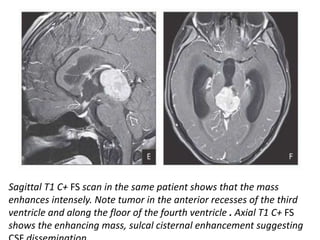

Sagittal T1 C+ FS scan in the same patient shows that the mass

enhances intensely. Note tumor in the anterior recesses of the third

ventricle and along the floor of the fourth ventricle . Axial T1 C+ FS

shows the enhancing mass, sulcal cisternal enhancement suggesting

DWI shows diffusion restriction. ADC map shows moderate restriction consistent with a highly

cellular mass. Germinoma